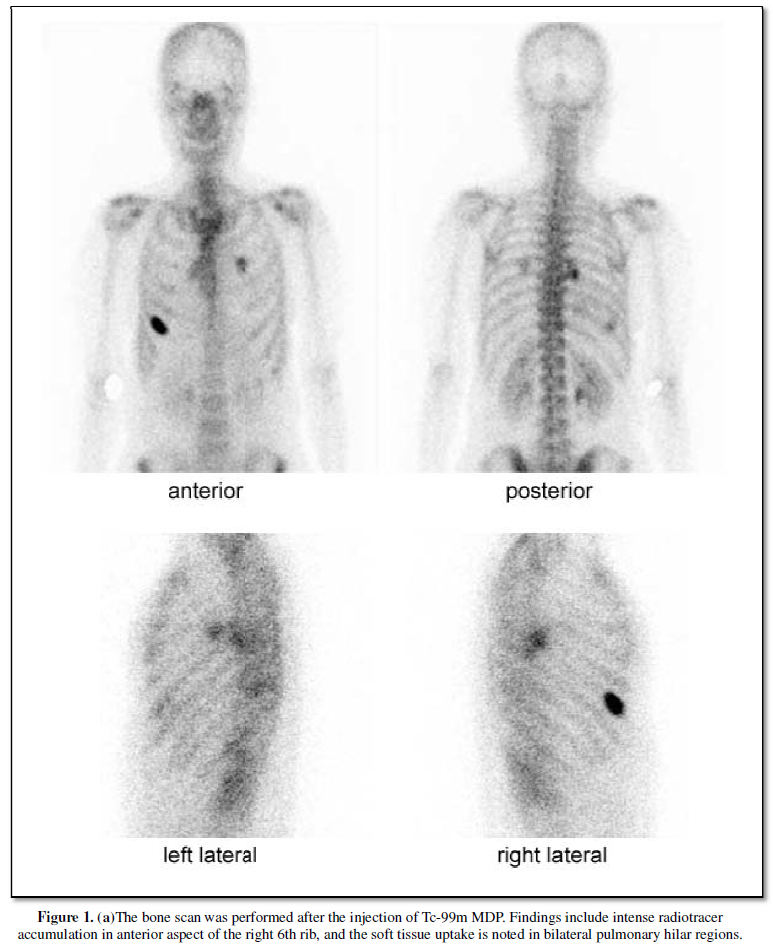

The bone scan was performed at three hours after the injection of 740MBq (20

mCi) Tc-99m MDP. Findings include intense radiotracer accumulation in the

anterior aspect of the right 6th rib. Additionally, soft tissue uptake is noted

in bilateral pulmonary hilar regions (Figure 1a). Unenhanced CT of the chest